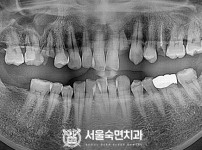

임플란트-전후사진4

치과를-선택할-때-꼭-확인하세요-서울숙면치과-임플란트-전후사진